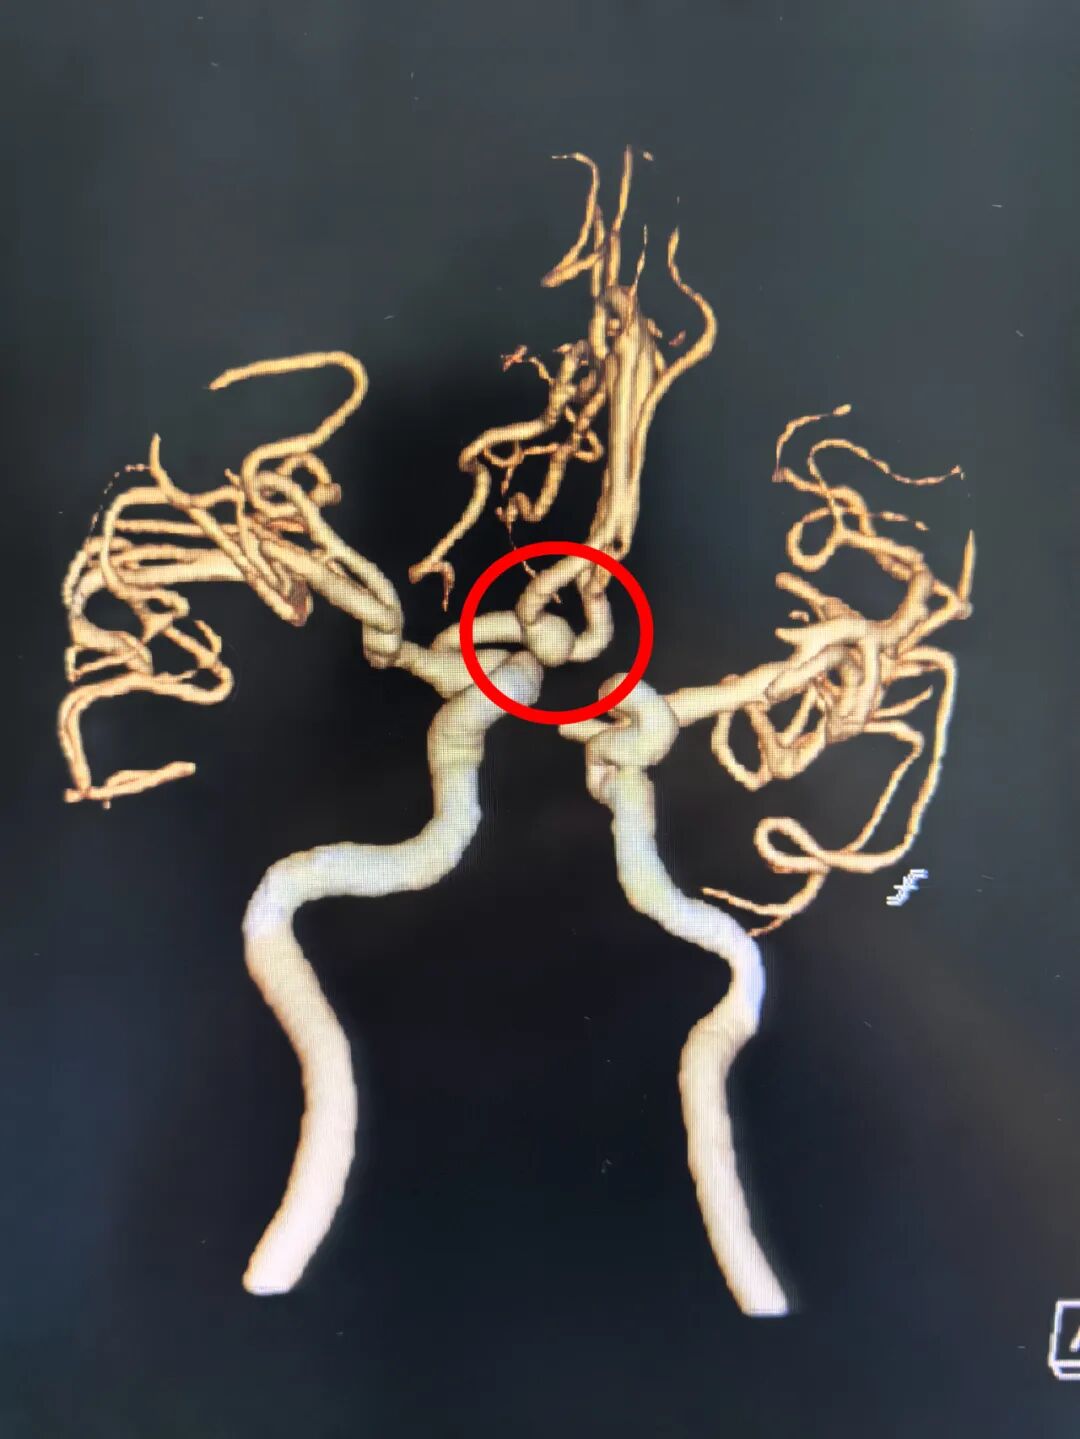

然而,进一步详细检查有了惊人发现:患者大脑前交通位置还存在一个致命的动脉瘤!先切除肿瘤还是先处理动脉瘤?这一难题让医生犯了难。

“必须尽快手术,赶在动脉瘤破裂前解决这两个问题。”惠州三院院长、神经医学中心主任李雪松博士强调。为此,李雪松博士带领团队多次组织病例讨论,结合患者的身体状况、肿瘤与动脉瘤的位置关系等因素反复推演手术步骤,最终制定了周密的手术方案:先切除右侧颞叶脑肿瘤,再行前交通动脉瘤夹闭术!

稍作调整后,手术团队立即转入动脉瘤夹闭环节。前交通动脉瘤位置隐蔽,操作空间狭小,对手术精度的要求高。李雪松博士全神贯注,在助手文世宏主任医师、刘洋主治医师的默契配合下,仔细游离动脉瘤颈,精准选择合适的动脉瘤夹进行夹闭。当确认动脉瘤完全闭塞且载瘤动脉血流通畅的那一刻,手术室内所有人紧绷的神经才稍稍放松下来。